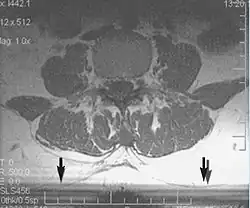

Flow can manifest as either an altered intravascular signal (flow enhancement or flow-related signal loss), or as flow-related artifacts (ghost images or spatial misregistration). Flow enhancement, also known as inflow effect, is caused by fully magnetised protons entering the imaged slice while the stationary protons have not fully regained their magnetization.[1] The fully magnetized protons yield a high signal in comparison with the rest of the surroundings. High velocity flow causes the protons entering the image to be removed from it by the time the 180-degree pulse is administered. The effect is that these protons do not contribute to the echo and are registered as a signal void or flow-related signal loss (Fig. 2).[1] Spatial misregistration manifests as displacement of an intravascular signal owing to position encoding of a voxel in the phase direction preceding frequency encoding by time TE/2.The intensity of the artifact is dependent on the signal intensity from the vessel, and is less apparent with increased TE.[1]